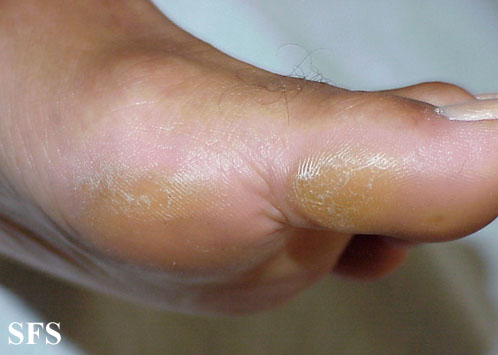

callus